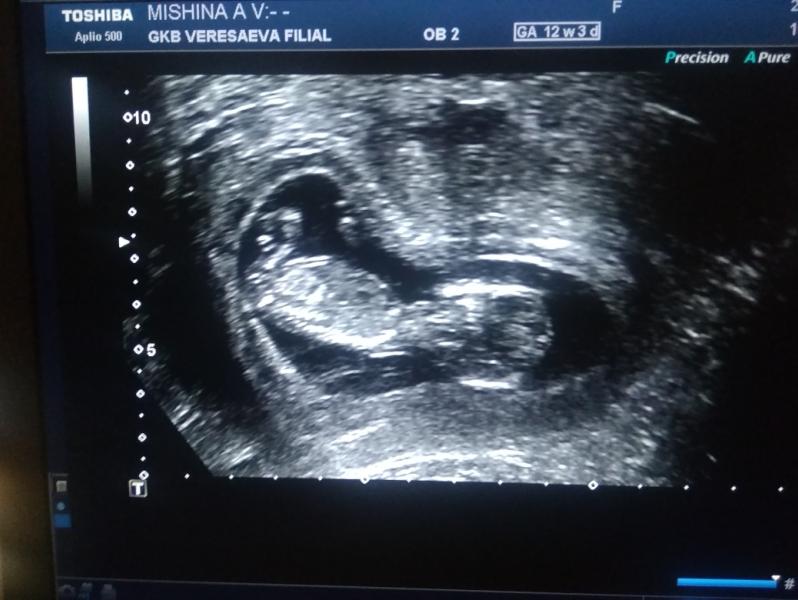

В 17 роддоме, пол рано ещё ))) хотя муж разглядел там мальчика ))))

Какой глазастый)) я после скрининга у мужа спросила: ну ты видел как она ротик открывала, а он говорит я видел черно белый экран 🙈🤣🤣

Ахаха ))) у меня был недоволен что потревожили , крутился там так активно